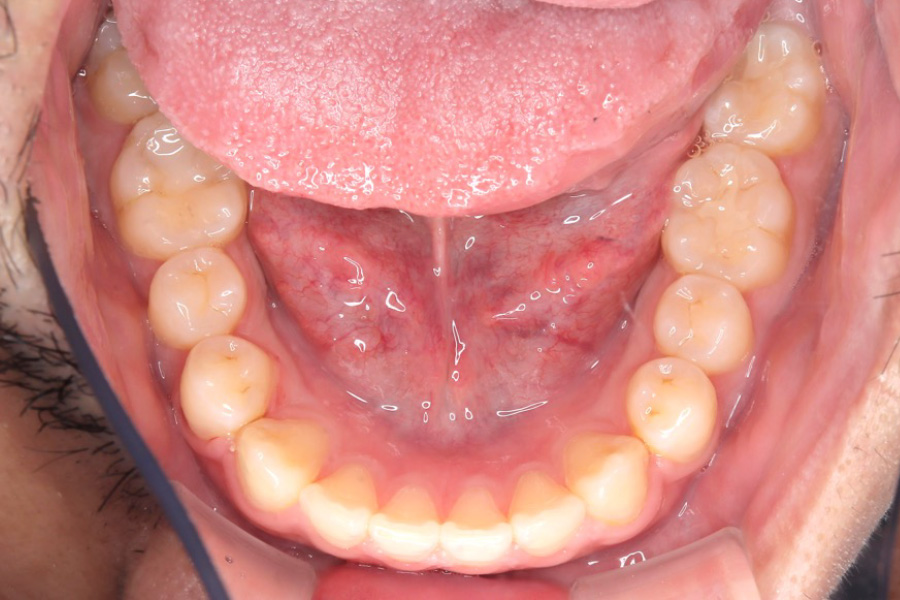

【20代男性】

歯の隙間を

インビザライン矯正で治療したケース

治療後

主訴 歯の隙間が気になる

治療内容 インビザライン矯正

非抜歯